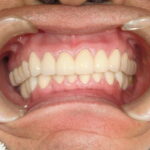

患者さんはとても満足されていました。

先端医療は患者様を幸せにします。これからも歯科バカでありたいと思います。